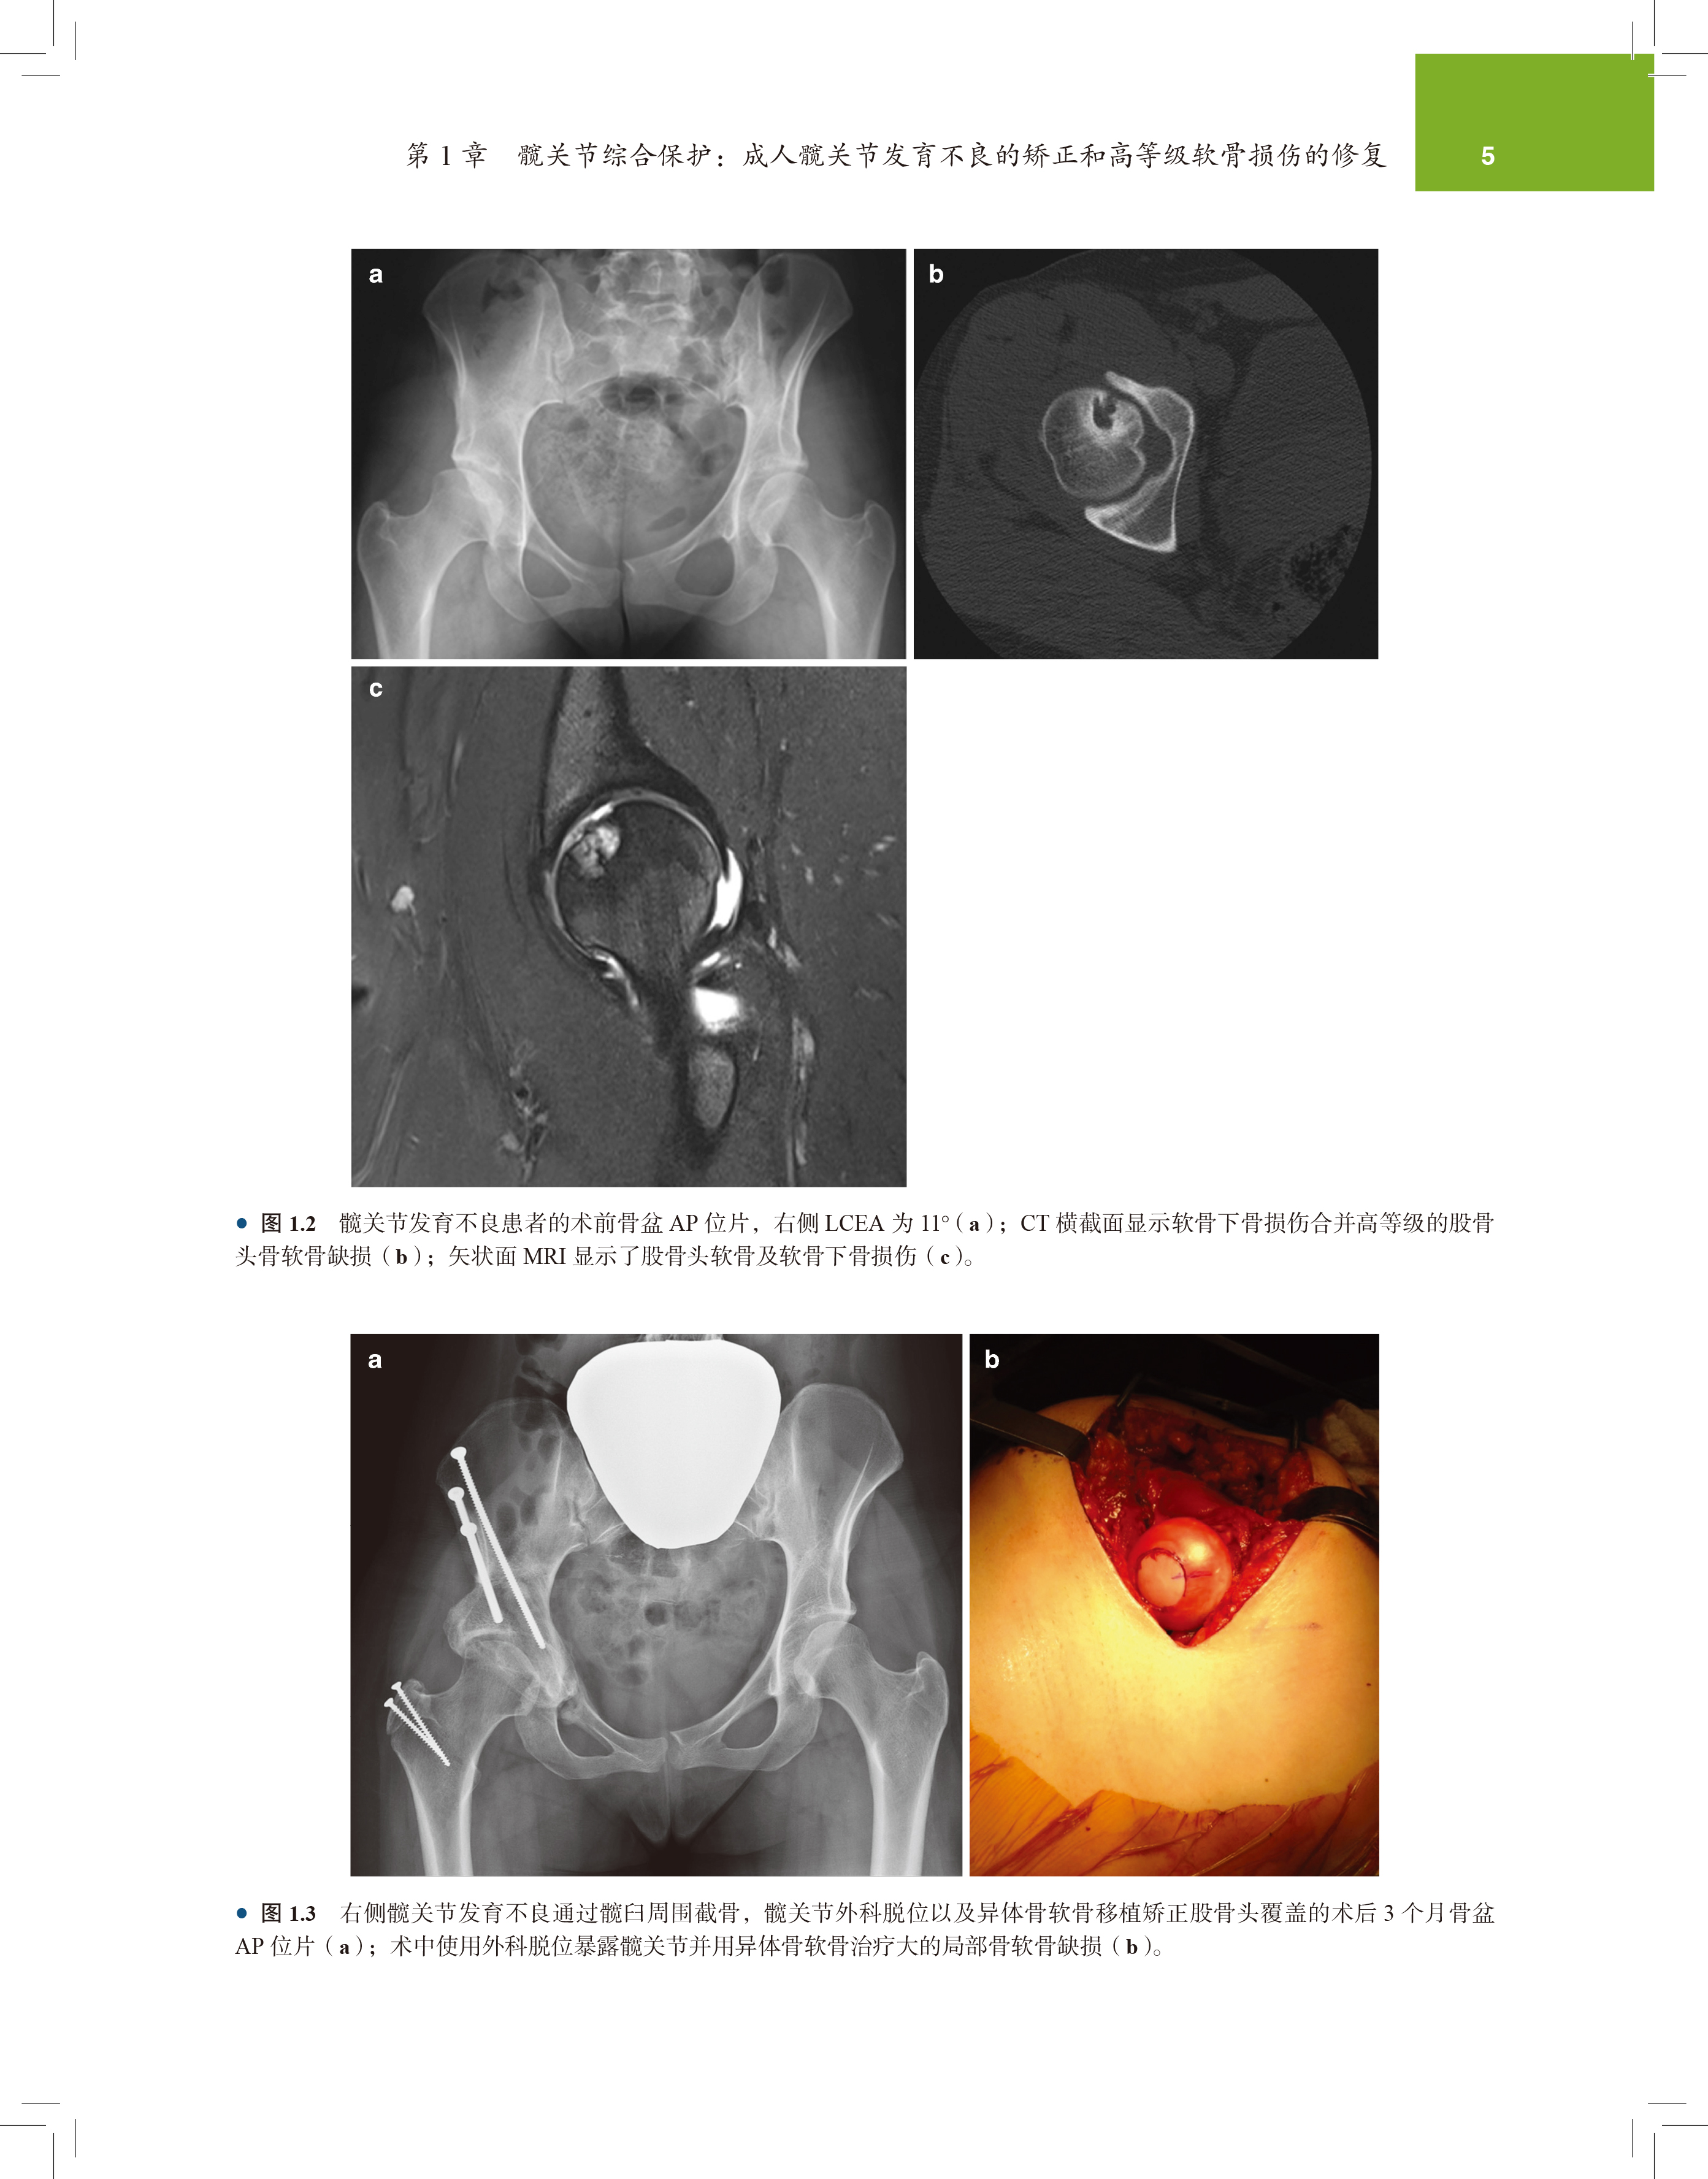

第 1 章 髋关节综合保护:成人髋关节发育不良的矫正和高等级软骨损伤的修复 2